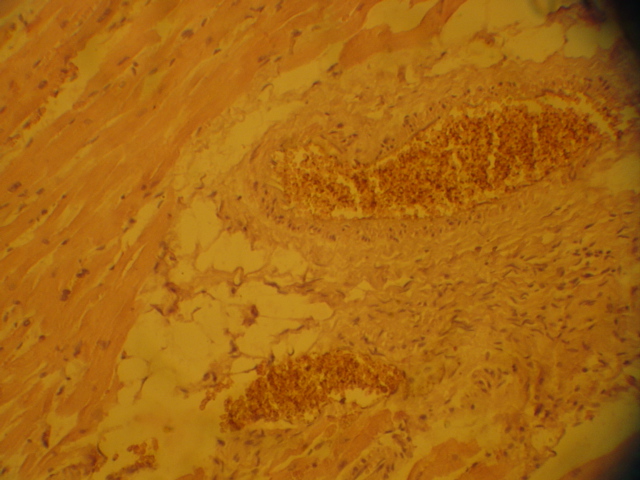

Миокард. Участок вокруг сосудистого пучка.Полнокровие.Разрастание соед ткани (кардиосклероз),небольшое стромальное ожирение (липоциты)

Эскизы прикрепленных изображений

На картинке, которую Вы смотрели (если смотрели) перенуклеарные скопления бурого пигмента! Это не липиды.

Это ЛИПОФУСЦИН - пигмент изнашивания (старения не по годам)!

Кроме того при КМП присутствет диффузный склероз с инфильтрацией лимфоцитами, фибробластами.

В диагнозе мы пишем: Коронарное заболевание сердца на почве кардиомиопатии с гипер- гипо- пластическими изменениями (очаговой атрофией) кардиомиоцитов, простым ожирением сердца с диффузным (илди другим) миокардиосклерозом.